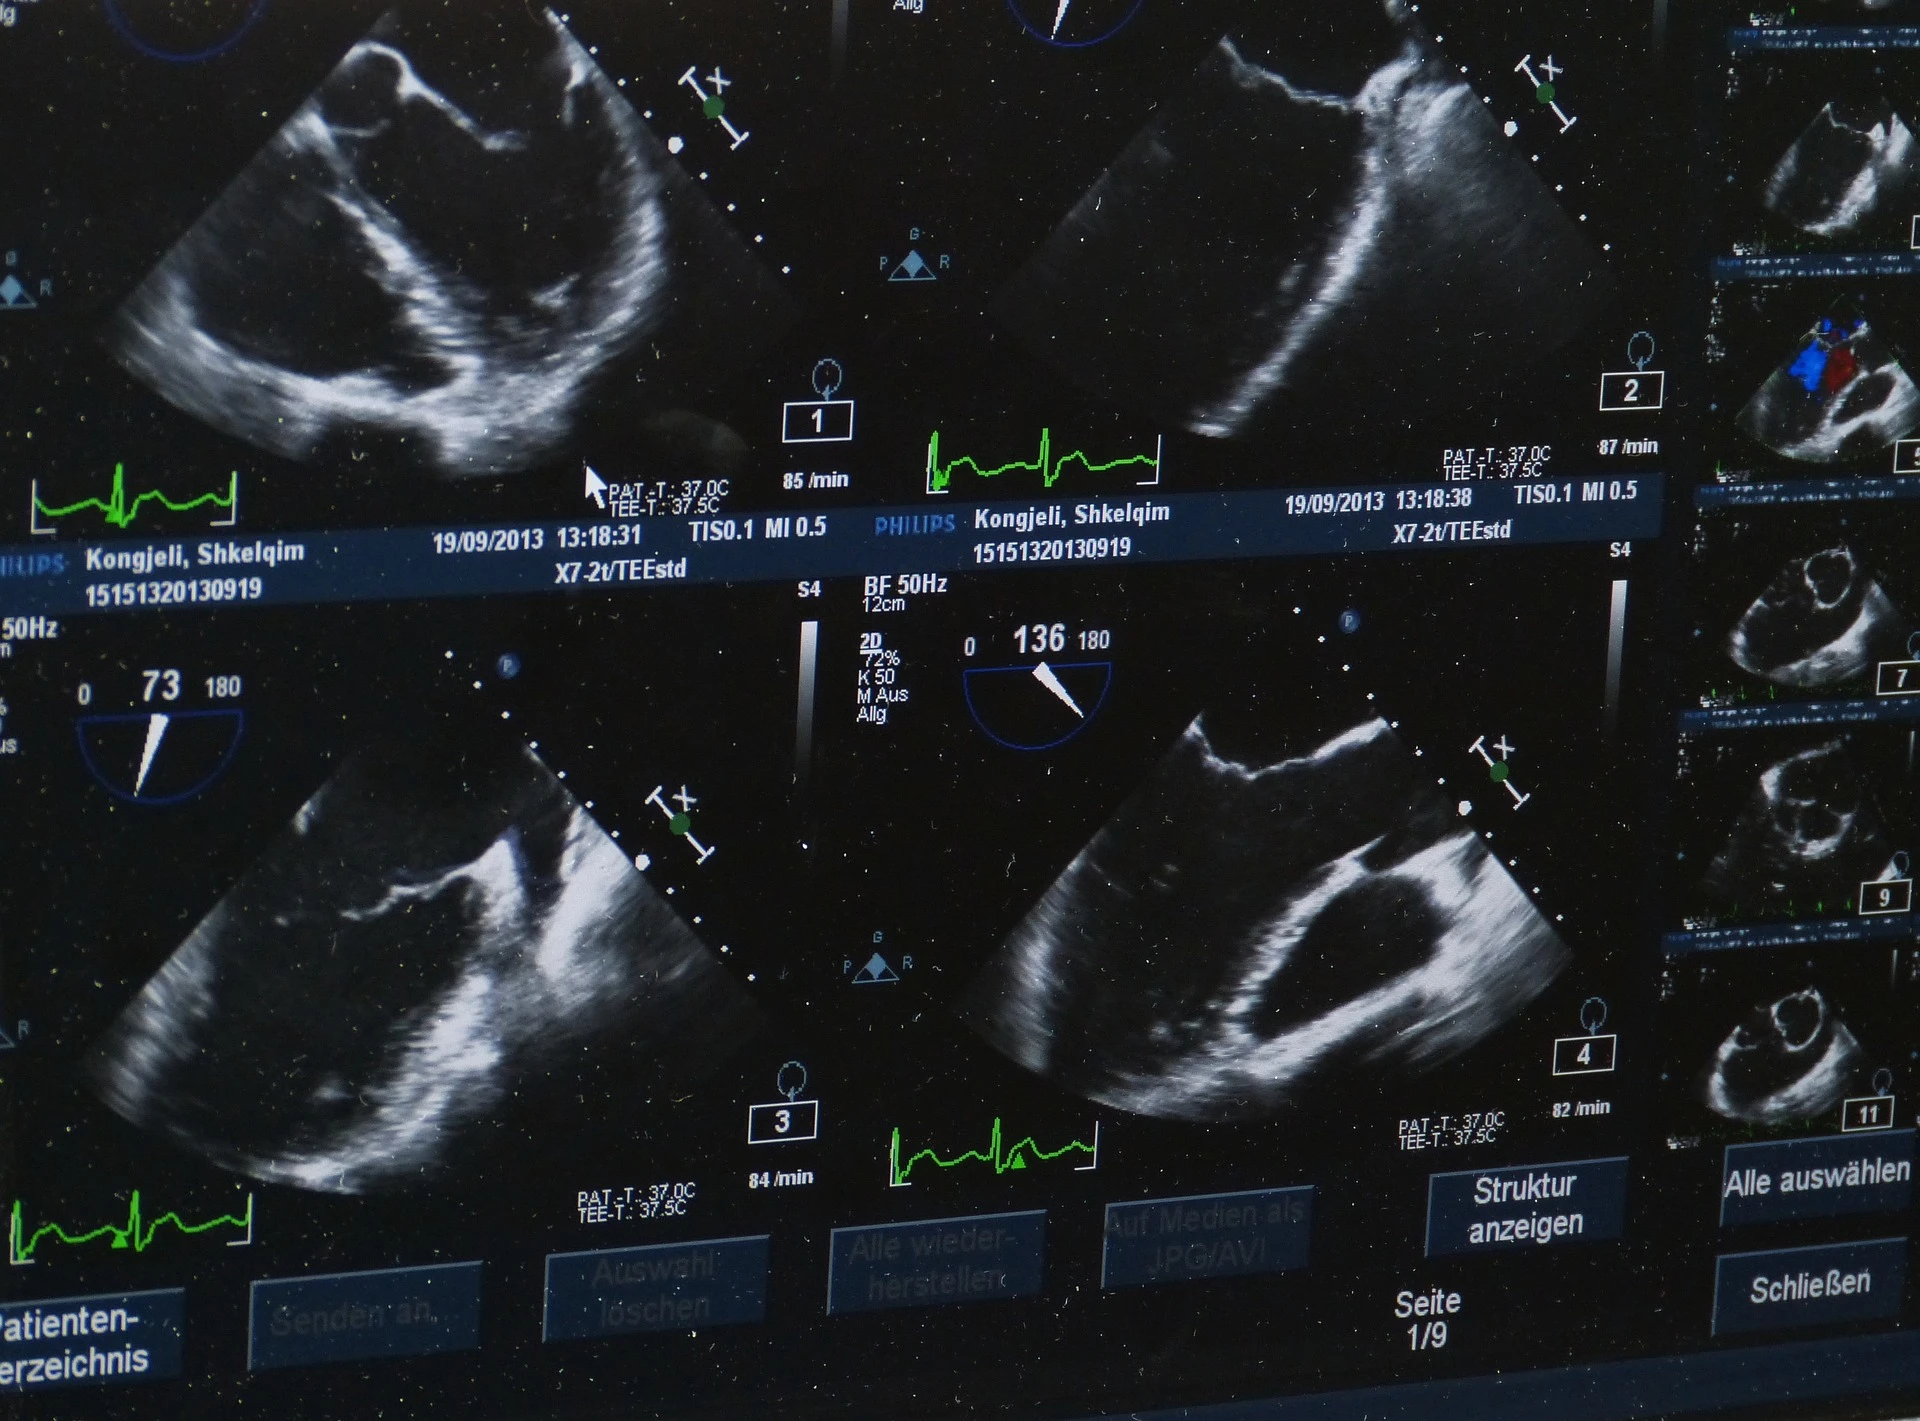

W większości przypadków mięśniaki macicy diagnozowane są podczas rutynowego badania ginekologicznego. Badanie ultrasonograficzne pozwala na dokładną ocenę wielkości, ilości, lokalizacji i rodzaju mięśniaków. W przypadku ich wykrycia zalecane jest wykonanie histeroskopiiLink otwiera się w nowej karcie diagnostycznej. Ten zabieg polega na wprowadzeniu do jamy macicy kamery umożliwiającej dokładne obejrzenie guzów, a dodatkowo pobranie wycinków do badania histopatologicznego. W przypadku licznych mięśniaków lub u pacjentek będących w wieku okołomenopauzalnym wykonywany jest rezonans magnetyczny i tomografia komputerowa miednicy celem kwalifikacji do myomektomii. Badaniem uzupełniającym jest rezonans magnetyczny.